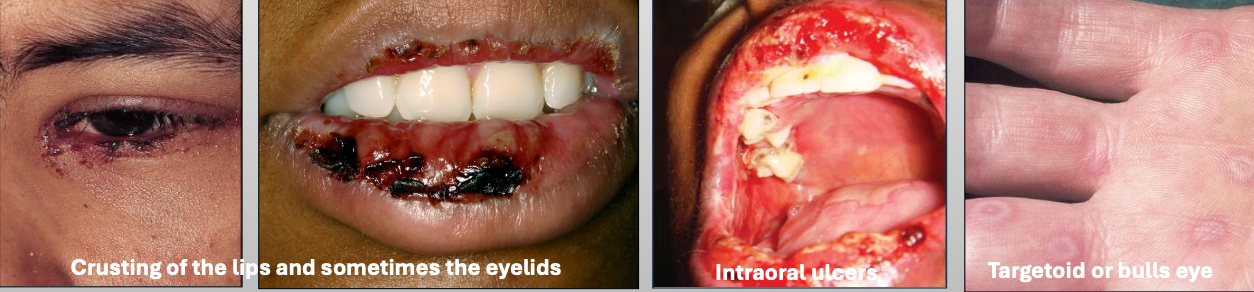

What are the clinical features of Erythema Multiforme (EM)

You get prodromal signs a week before

Crusting of the lips and sometimes the eyelids

Intraoral ulcers

Targetoid or bulls eye

What are characteristics of minor Erythema Multiforme (EM)?

Mild

Young, Male > female

Starts on skin of extremities, oral lesions appear

Crusting on lips

Usually due to herpes (HSV)

What are characteristics of major Erythema Multiforme (EM)?

Wide spread skin lesions + 2 or more mucosal sites

(Oral + ocular or genital)

Ocular scarring may occur in severe cases (Symblepharon)

Usually due to herpes (HSV)